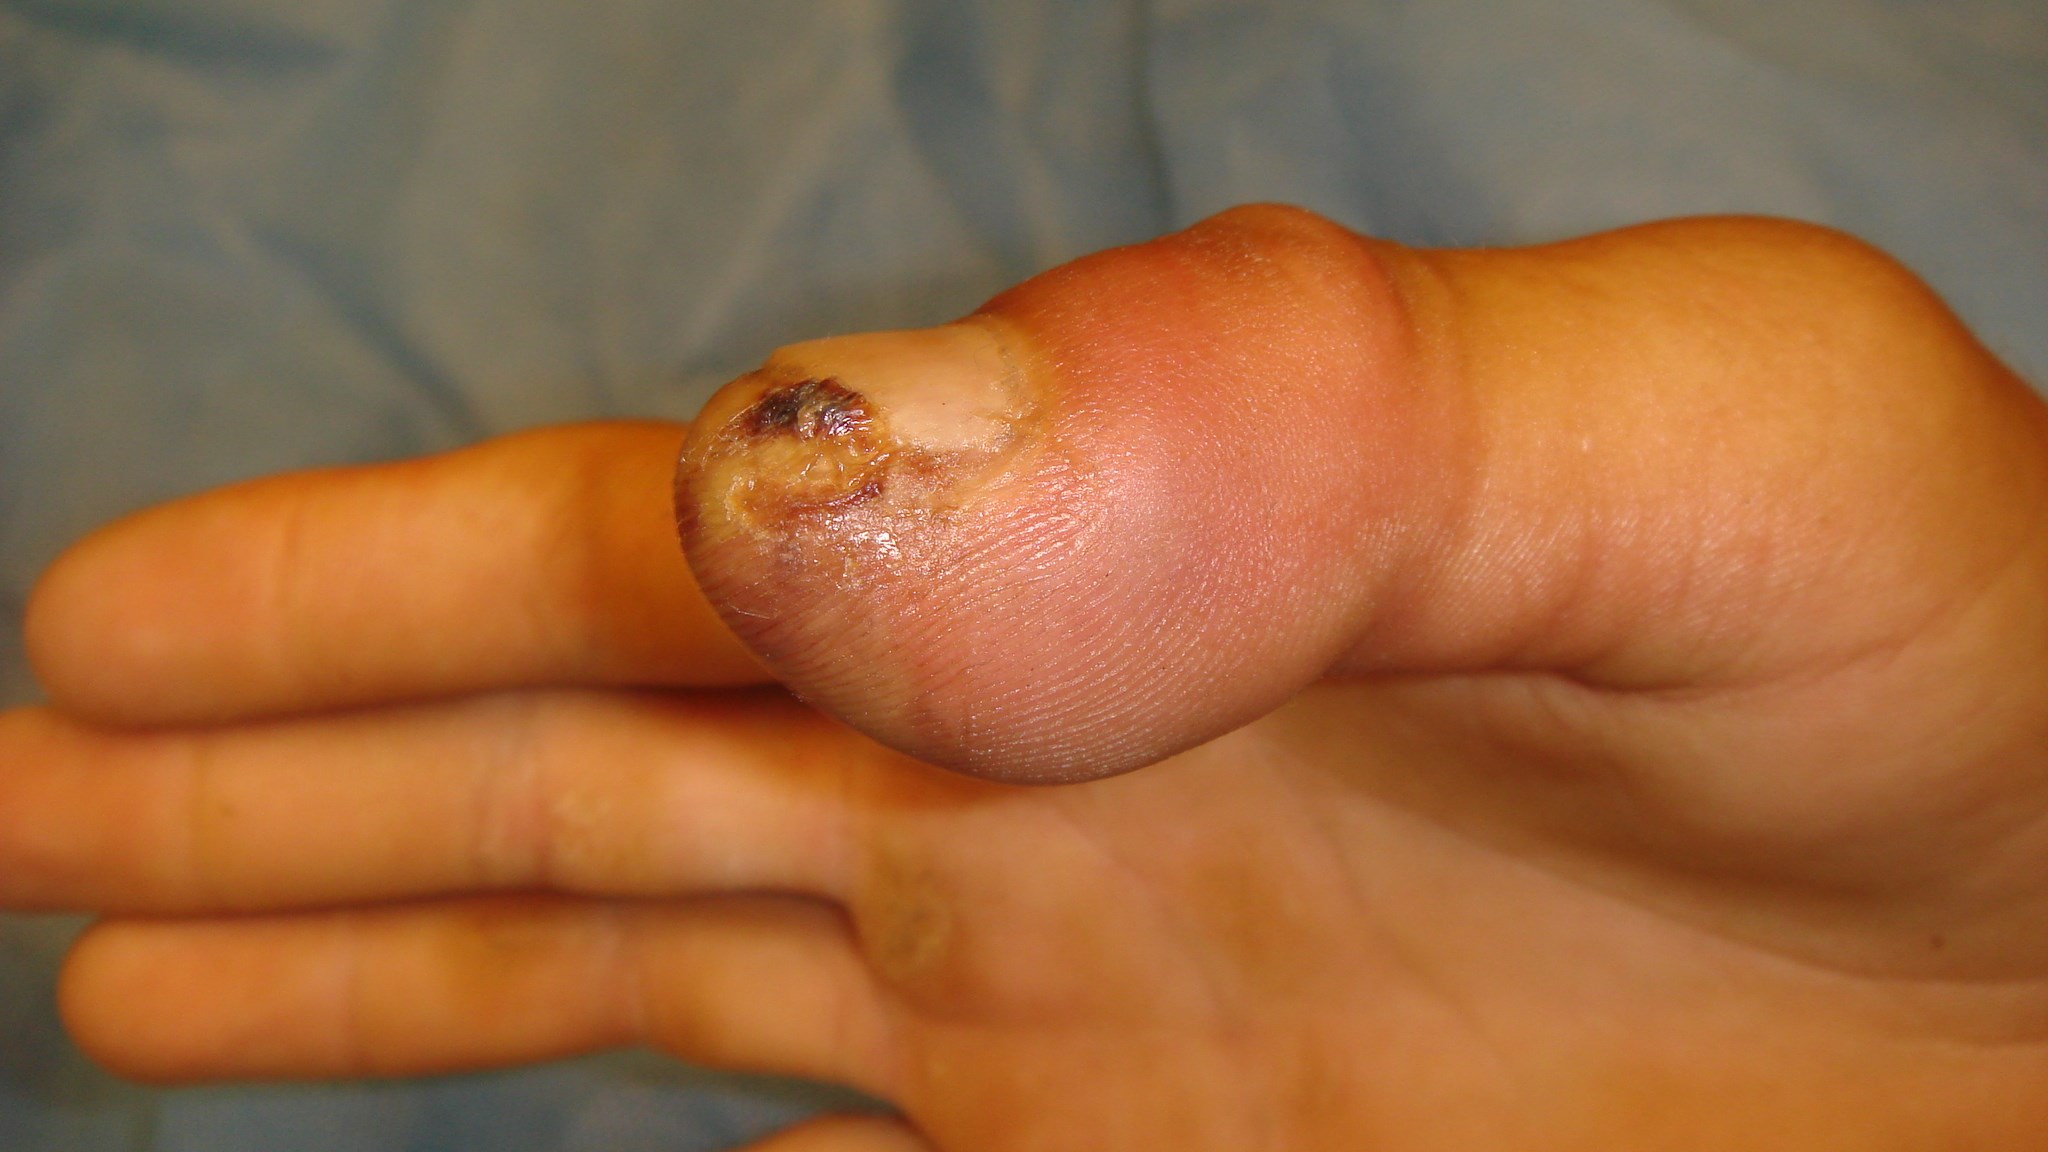

Fingertoppsskador

Fingertoppsskada utan blottlagt ben

Fingertoppsskador utan blottlagt ben behandlas vanligen bäst med konservativ regim. Det vill säga initial rentvättning av såret och därefter omläggningar med förband som inte helt torkar ut sårytan. Läkningen bygger på att epitelet växer in från sidorna av sårkanten varför det kan ta flera veckor eller månader innan toppen är fullt läkt.

Att det är mödan värt att vänta beror på att man slipper korta fingret eller tummen ytterligare för att få primär sårläkning. Hudtransplantat är ett annat alternativ men jämfört med det blir både form och kvalitet på toppen betydligt bättre efter sekundärläkning.

Fingertoppsskada med blottlagt ben

Fingertoppsskador med blottlagt ben läker inte på konservativ behandling eftersom de dermala cellerna inte förmår att växa in och täcka benvävnaden. Förutsättningarna för att hudtransplantat skall överleva är också mycket dåliga.

Den primära åtgärden blir därför att nypa ned benet till en nivå som ligger under mjukdelarnas yta. Använd en bentång och trimma benet till en jämnt rundad form.

Förstahandsalternativet är att recessera tillräckligt med ben för att man primärt skall kunna suturera sårkanterna till varandra. Observera att det inte får vara för spänt eftersom cirkulationen i kanterna av såret då blir dålig vilket ger risk för nekros, infektion och sårruptur. Nagelbädden får inte heller sys ned för att använda som täckning eftersom det kan leda till s.k. klonagel eller andra nageldeformiteter som är mycket störande för patienten.

Ett annat alternativ är att man först trimmar ned benet och om mjukdelarna täcker benet får såret sedan sekundärläka men det är en mer osäker och tidskrävande metod. Avseende fingrarna prioriteras läkning och stumpens kvalitet före längd. Det innebär att man ofta tvingas korta benet något för att täcka toppen med viabel hud av god kvalitet.

När det gäller tummen är situationen annorlunda och här gäller det omvända, att bevara längd till varje pris. Är benet blottlagt i tummens topp bör fallet därför diskuteras med handkirurg gällande eventuell täckning med hjälp av hudlambå. Lambåtäckning i detta fall innebär att med olika tekniker förskjuter eller förflyttar hud med bevarad cirkulation. Området man ”lånar” ifrån kan ligga mer proximalt på fingret, på ett angränsande finger eller i handflatan.